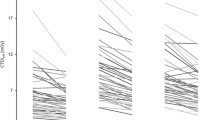

There was a significant positive correlation between DAP value and body weight (Fig. 3A; r = 0.76, slope 0.238 Gycm2/kg, p < 0.001) as well as ED and body weight (Fig. 3B; r = 0.55, slope = 0.045 mSv/kg, p < 0.001). The conversion factor ED per DAP decreased with increasing body weight (Fig. 3C; r = 0.99, slope = −0.00279 mSv/Gycm2kg, p < 0.001 for upper abdominal CBCT and r = 0.99 slope = −0.00197 mSv/Gycm2kg, p < 0.001 for lower abdominal CBCT). Adding patients’ body height as an independent variable into the regression models yielded no significant regression coefficients for height (p > 0.05).